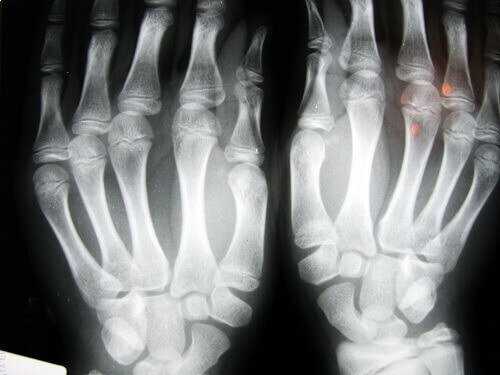

De personen die vaak aan dit probleem lijden zijn volwassenen van 40 jaar en ouder en de gebieden waar het kraken van gewrichten de meeste afbraak veroorzaakt zijn de handen (vingers en polsen) en in de nek.